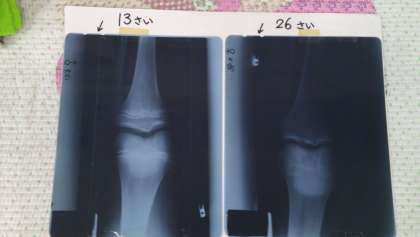

骨の伸びる部分「成長軟骨」の写真と絵を見ながら、イメージしました。

骨が長く強くなるのは、成長ホルモンの影響であり、寝ている間にたくさん出ることを知りました。だから、今の成長期には、睡眠が大切であることを理解できたと思います。